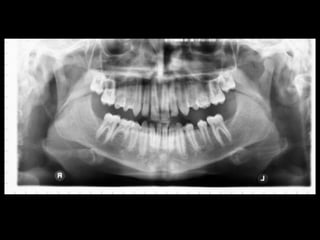

Panoramic (reconstructed from CT)

The most likely diagnosis for the facial asymmetry of this young girl is an

undiagnosed condylar fracture that most likely happen when she falled on a meta

crossbar bar ladder 2 or 3 years ago while she was 4 - 5 years old or so. The

condylar stump has healed and a new condylar head has formed, but the losted

substance of the condyle is gone. Therfore, the height of the ramus has

shortened.

The left ramus and condylar neck are shorter and the left eminence has no slope

if any. Healing and normal growth had reshaped both condyle and eminence.